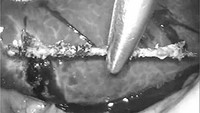

Jarum jahit sepanjang sekitar 3 cm berhasil diangkat melalui operasi laparoskopi. Pasien pulih dengan baik dan dipulangkan empat hari setelah operasi tanpa komplikasi. (Foto: Journal of Surgical Case Reports)